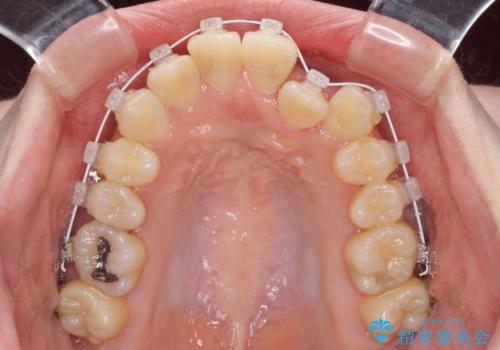

- 審美装置

- 1年3ヶ月

- 10-30回

マウスピースによる矯正治療も提案しましたが、ご自身でのマウスピースの管理の面倒くささと、なるべく早く治療を終えたいとのことで、ワイヤー矯正を選択されました。